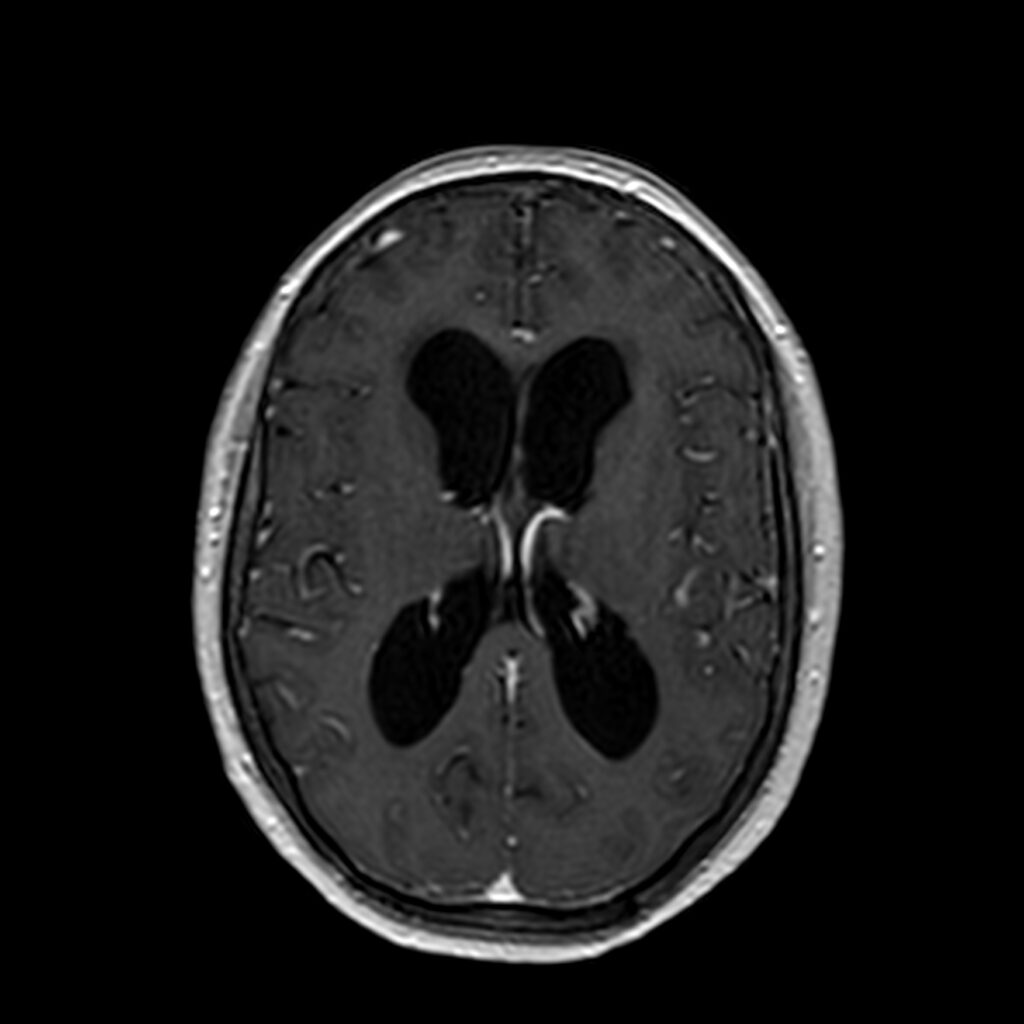

Hidrocefalia

Existen dos tipos de hidrocefalias: aguda y crónica. La hidrocefalia aguda ocurre de manera abrupta por la interrupción de la circulación de líquido cefalorraquídeo, y esta obstrucción debe salvarse para aliviar la presión intracraneal y salvaguardar la vida del paciente.

El diagnóstico se fundamenta en una entrevista clínica minuciosa, una prueba de resonancia magnética, y otros tipos de pruebas complementarias como el test de infusión o el tap test. Poder determinar aquellos pacientes que se beneficiarán de la colocación de un sistema derivativo del líquido cefalórraquídeo (o válvula) exige un estudio concienzudo y exhaustivo.